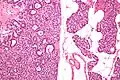

Micrograph of a parathyroid adenoma (left) and normal parathyroid gland (right). H&E stain.

Hyperparathyroidism is confirmed by blood tests such as calcium and PTH levels. A specific test for parathyroid adenoma is sestamibi parathyroid scintigraphy, often referred to as sestamibi scan or, more colloquially, MIBI scan. This nuclear imaging technique reveals the presence and location of pathological parathyroid tissue.[7] In cases where 99mTc-sestamibi scintigraphy or SPECT delivers inconclusive results, other imaging modalities and tracers can be applied. For detection of multiple parathyroid adenomas, positron emission tomography (PET) using the radiopharmaceutical 68Ga-Trivehexin[8] has demonstrated a higher detection rate (94.1%) than 99mTc-sestamibi imaging (58.8%).[9]